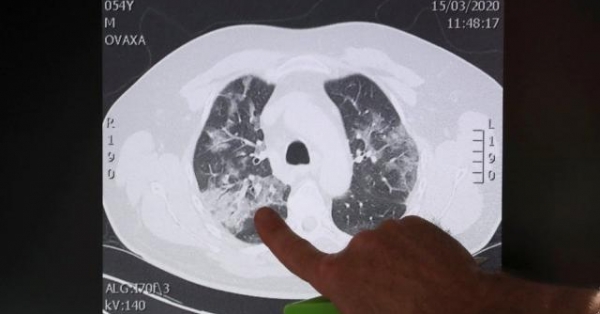

SARS-CoV-2 là một loại virus thuộc họ corona, được biết đến với phương thức tấn công vào hệ hô hấp, gây ra các triệu chứng giống cúm thông thường như ho khan và sốt. Các công trình nghiên cứu trước đây chỉ ra rằng bệnh nhân mắc Covid-19 sẽ bị tổn thương phổi lâu dài. Tuy nhiên, hậu quả của bệnh chưa dừng lại ở đó.